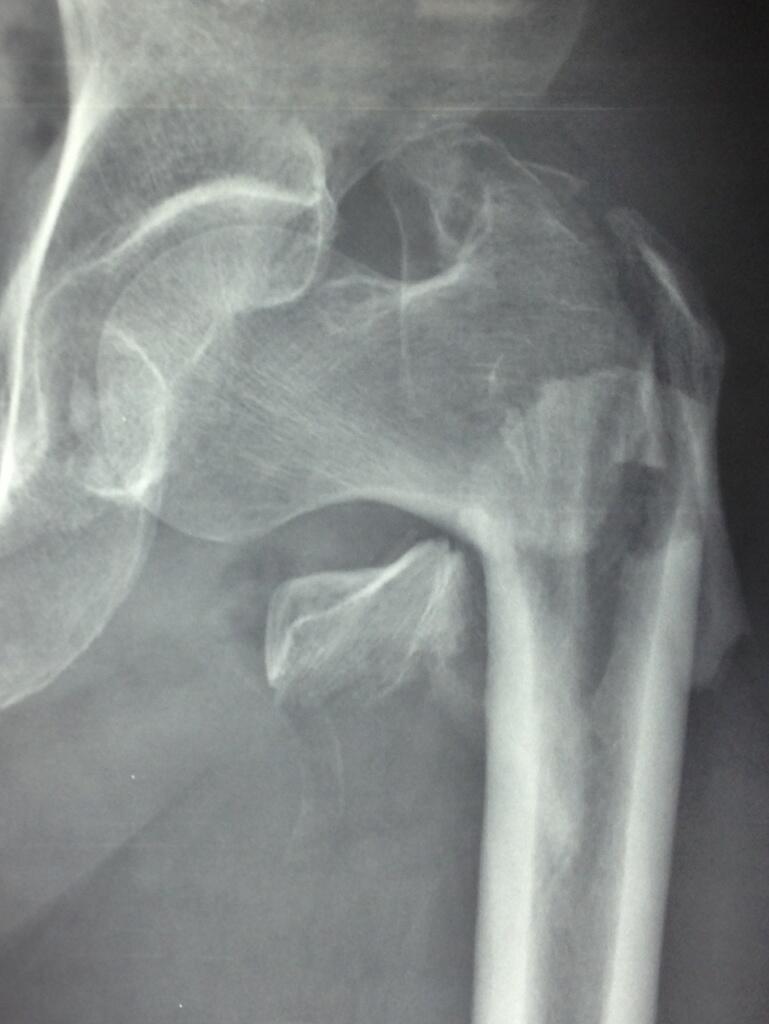

complex #hip #fracture

First case today: complex our plan: minimal invasive surgery with nail pic.twitter.com/5RwXacqLb1